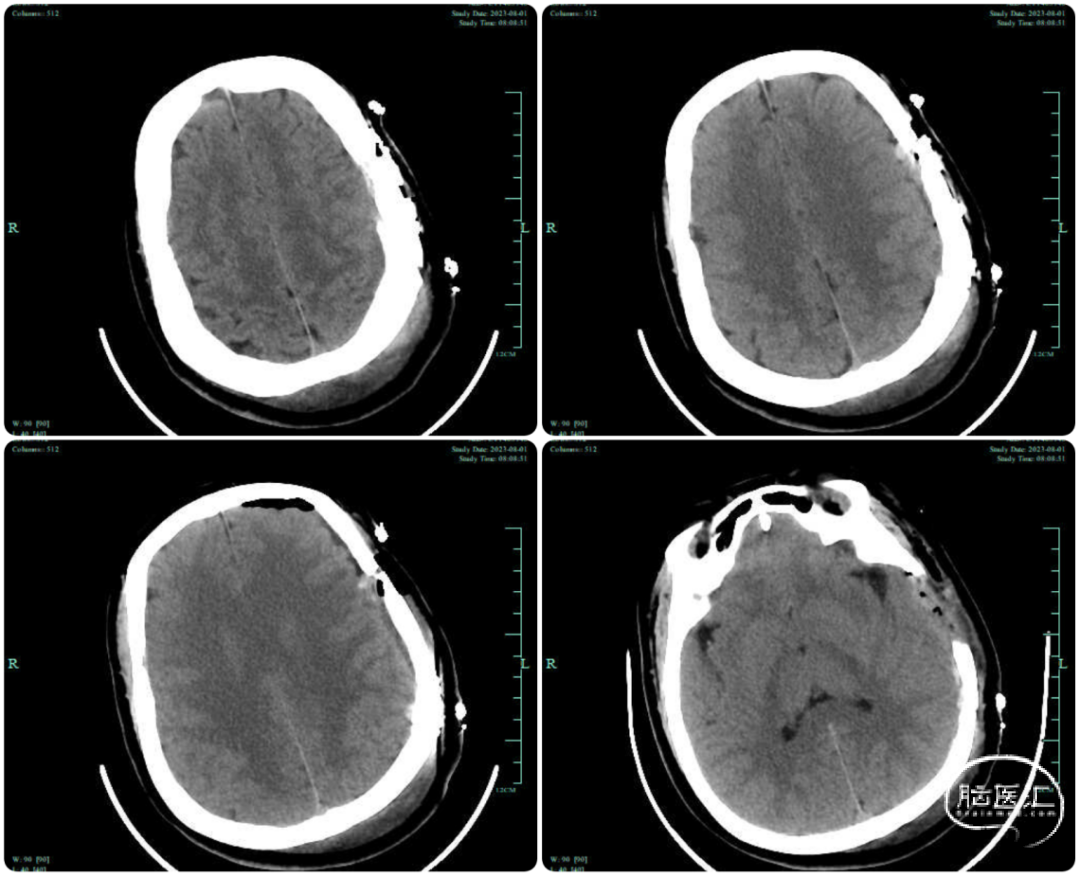

脑血流灌注检查:(图2)。MR检查未见明显脑梗死等改变。

图2. (左侧中动脉供血区r-CBF↓ ,TMax↑,MTT↑)